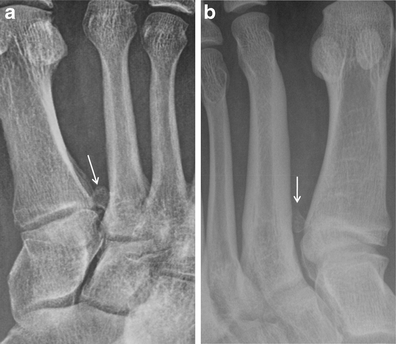

Osteomyelitis. a AP radiograph in a patient with a plantar ulcer showing cortical dehiscence and destructive change at the medial sesamoid (black arrow) suggestive of osteomyelitis. Note severe adjacent soft tissue swelling (white arrow). b AP radiograph in the same patient approximately 5 weeks later with near complete destruction of the medial hallucal sesamoid (black arrow) and persistent soft tissue swelling (white arrow). The great toe was amputated